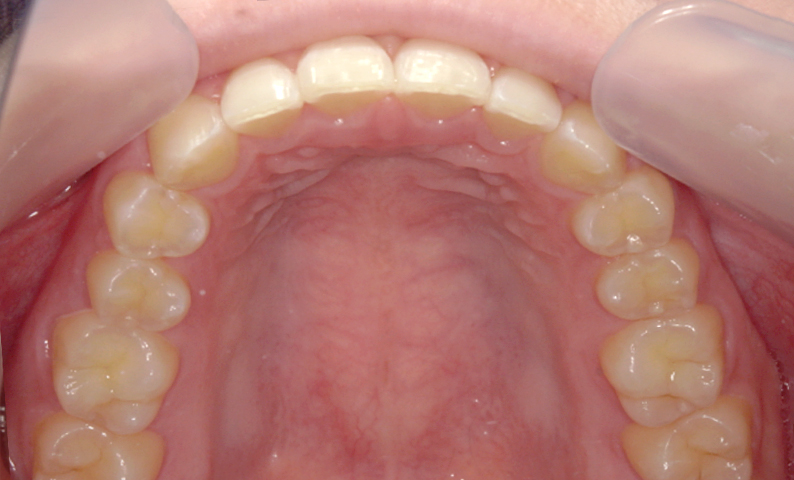

| 治療前 | 治療後 |

|---|---|

|